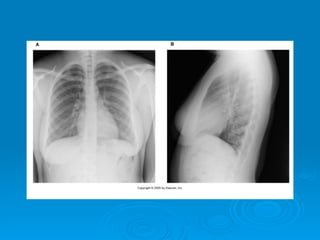

CIFOSIS:

Es un aumento de la curvatura

dorsal por causas patológicas.

Común en adolescentes en el

periodo de crecimiento.

ALTERACIONES DE LACOLUMNA VERTEBRAL CIFOSIS: Es un aumento de la curvatura dorsal por causas patológicas. Común en adolescentes en el periodo de crecimiento.